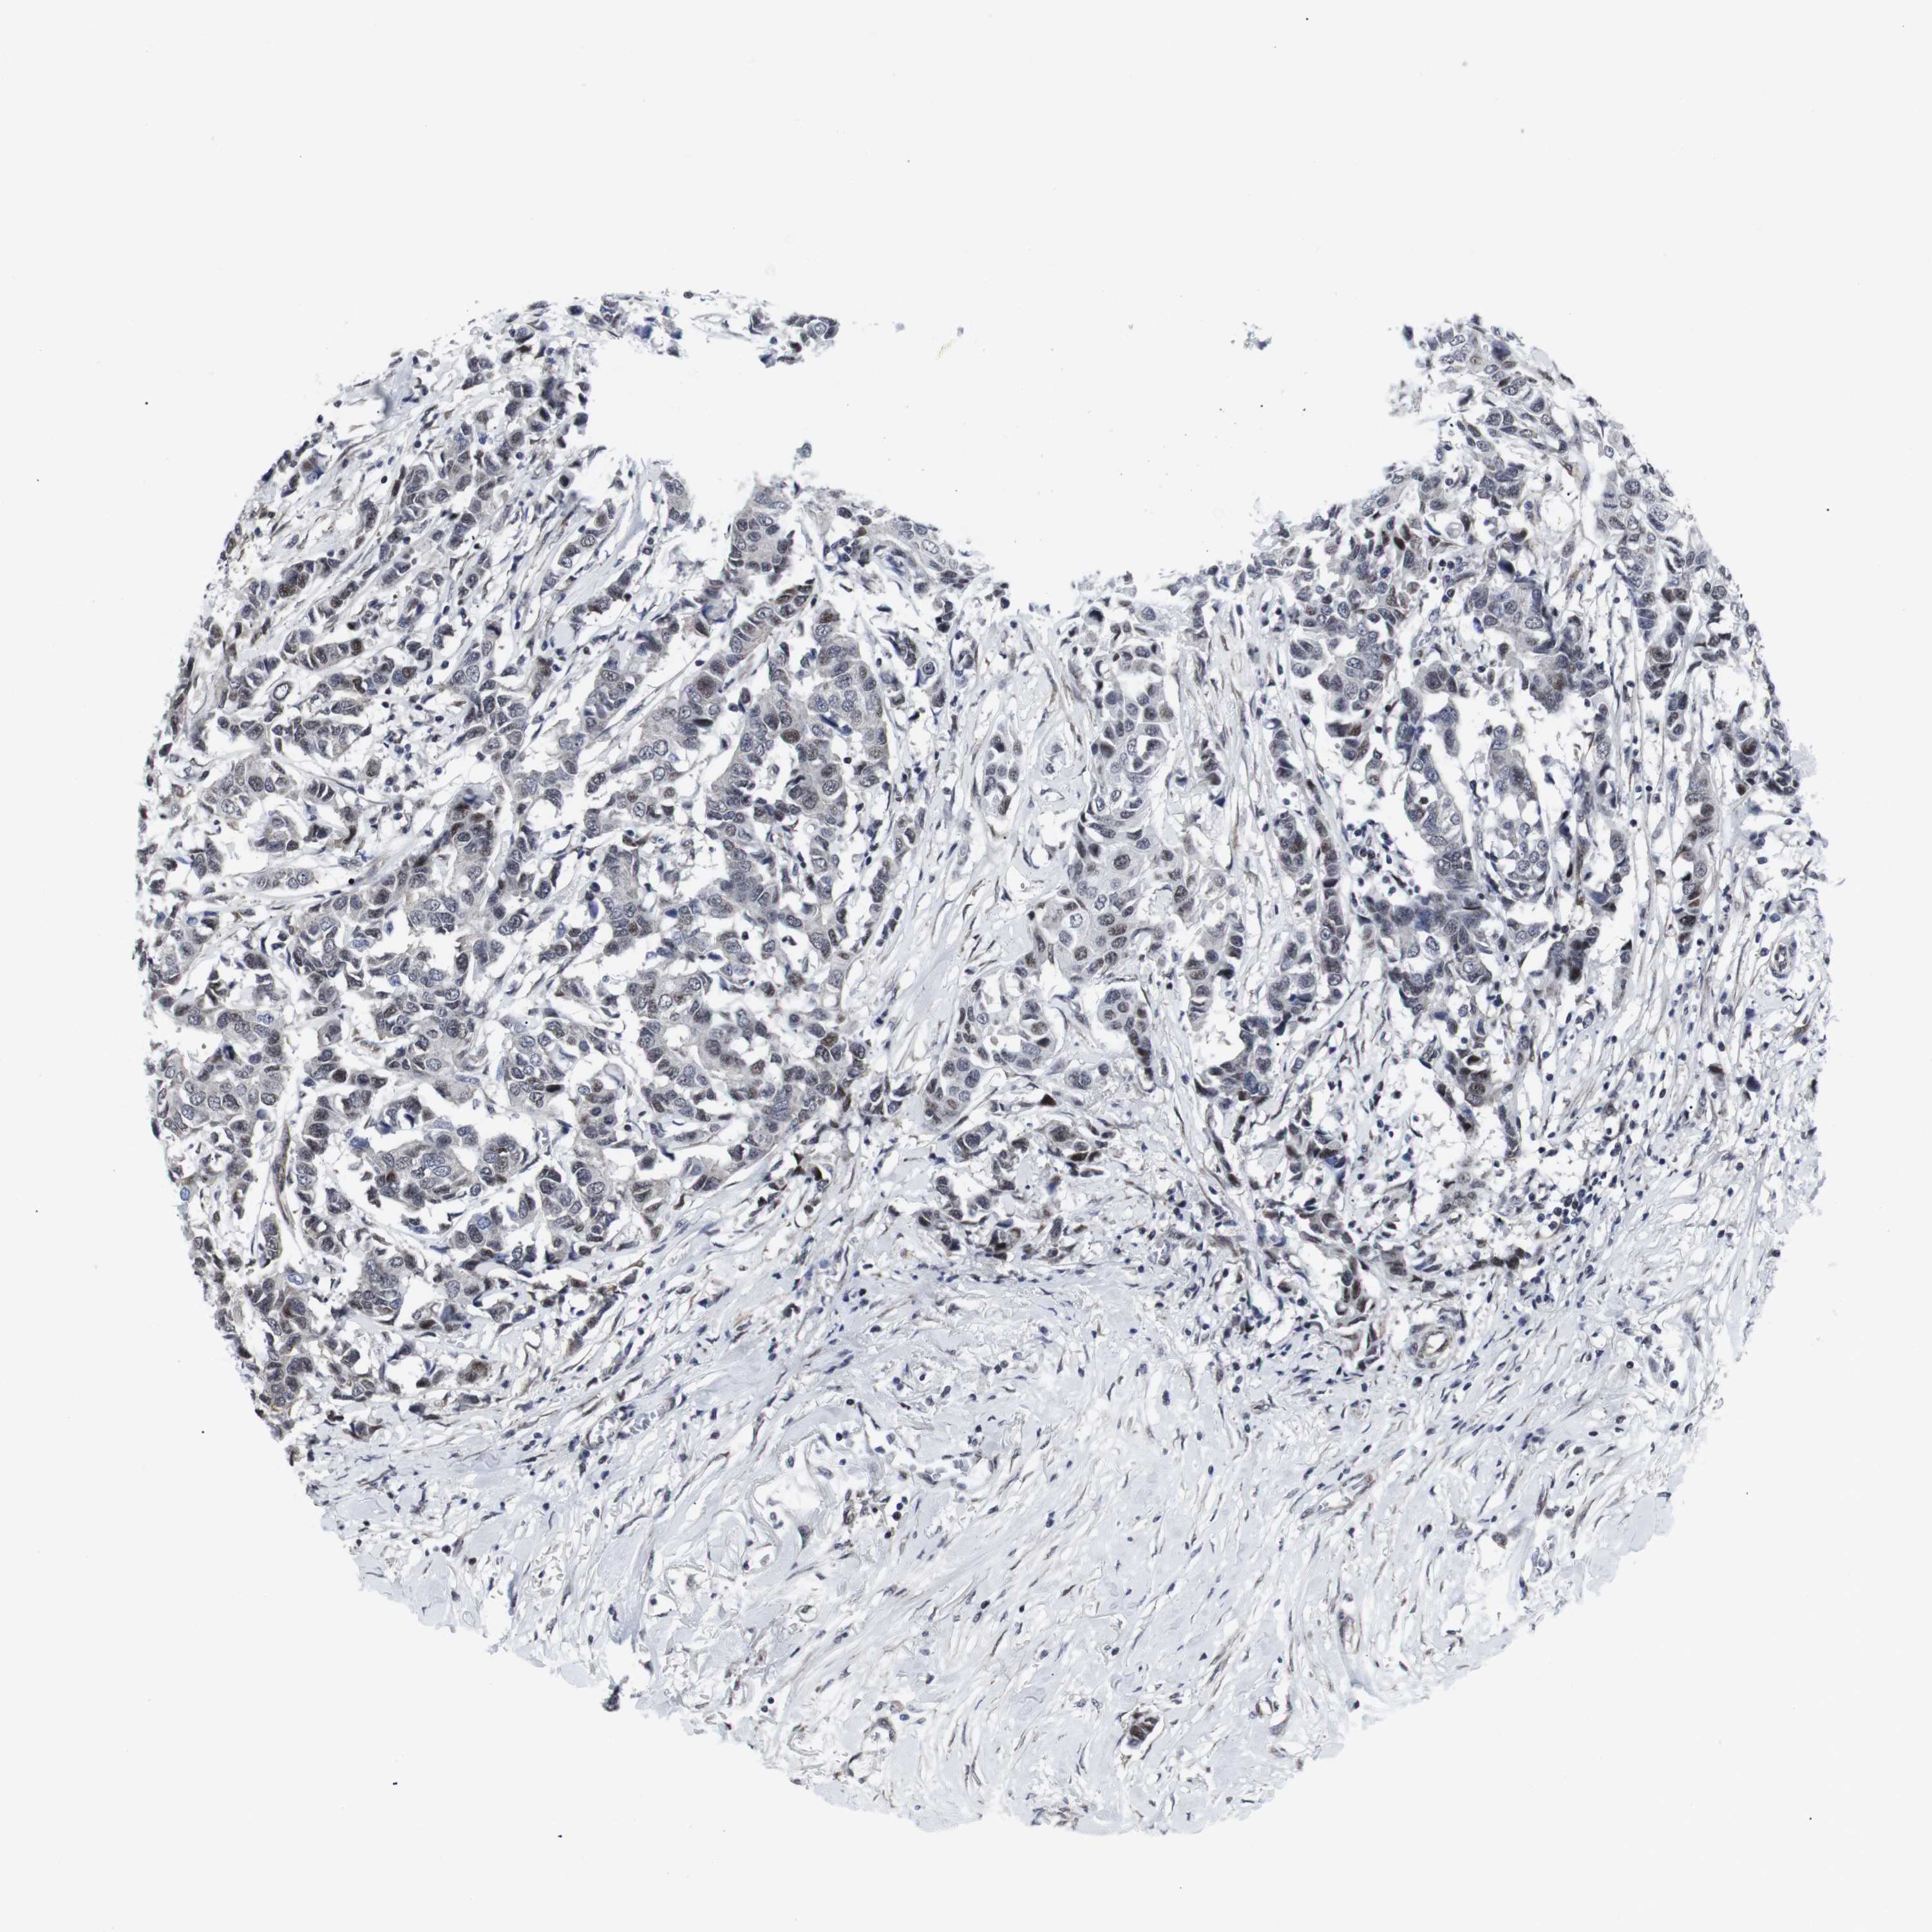

CANCER BREAST CANCER Show tissue menu

BRCA TCGA BRCA VALIDATION PROTEIN EXPRESSION